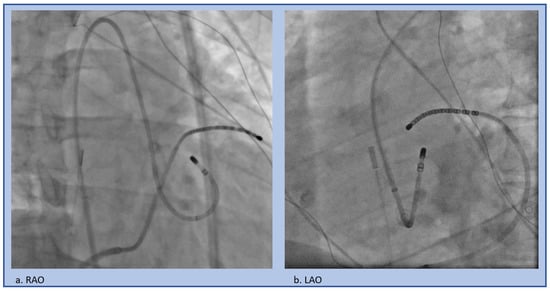

2.2. Catheter Ablation

4.2. Catheter Ablation

5.2. Catheter Ablation Considerations

6.2. Catheter Ablation